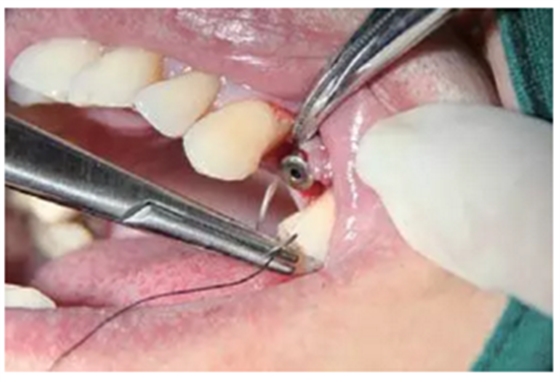

圖6 放入愈合基臺并縫合

種植完成

種植完成后可以通過拍攝曲面體層或是根尖片來確認(rèn)種植體的植入情況,并作為資料加以保存。

種植手術(shù)完成2周后進(jìn)行拆線??梢钥闯鲕浗M織愈合良好。